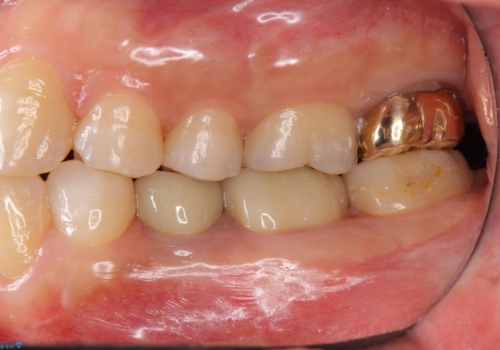

手術後は半年仮歯で過ごしていただいた後、歯肉の高さが決まってからセラミッククラウンを装着していきます。

- 44万円 左下5:仮歯、セラミッククラウン 左下6:精密根管治療(再治療)ファイバーコア、仮歯、セラミッククラウン費用は治療当時の料金となります